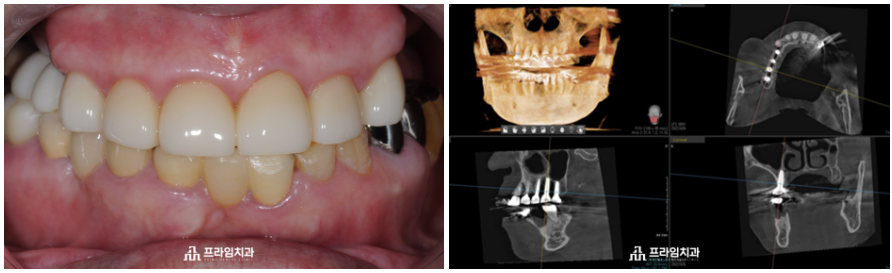

오늘은 매직 코어 임플란트를

진행하신 환.자분을 소개해 드리려고 합니다.

위 환자분은 88세 여성분으로

전주에 혼자 거주하고 계시는 분이신데요.

치과 공포증으로 인해 여태까지

치료를 미루고 계셨다고 하셨습니다.

윗니가 앞니 6개만 남아 있는 채로

10년 넘게 앞니로만 식사를 하고 계신 상태로

경제적인 여유가 충분하나 임플란트 수술이 무서워

치료를 포기하고 계시다가 큰마음 먹고

.

임플란트를 하기로 결정하고 난 후

자제분이 계신 서울의 치과 몇 군데에서

상담을 받으시고 오셨다고 하셨습니다.

그러던 중 저희 치과에 내원해 주셨고

무절개임플란트에 관한 설명을 들으시고

타치과에서는 잇몸뼈 이식을 해야 한다고

설명 들으셨지만

잇몸뼈 이식 없는

매직 코어를 이용한 본원의 편안한 임플란트

설명을 들으시고 진행하기로 하였습니다.

환자분의 잇몸 상태를 충분히

고려하여 전주임플란트치과에서는

매직 코어 최소침습 임플란트

수술의 장점을 설명드린 후

진행하였습니다.

절개를 하는 과정이 없어

수술 시간이 짧았는데요.

저희 치과에서는 임플란트

식립 전 3D CT와 구강 스캐너를

활용하여 육안으로 판단하기

힘든 구강 해부학적 구조물과

혈관 및 신경의 위치까지 면밀히

파악하여 1:1 맞춤 치료 계획을

수립하고 있습니다.